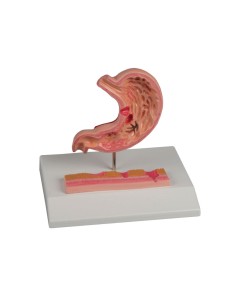

Scopri il Mondo dell’Anatomia con Modelli anatomici di Precisione

Modelli Anatomici Dettagliati per Ogni Necessità

Dal cranio in 22 parti con incastri magnetici ai modelli di colonna vertebrale, da quelli di articolazioni a quelli di cuore, ogni pezzo della nostra collezione è progettato per un’immersione totale nello studio dell’anatomia umana. I nostri modelli, realizzati tramite scansioni di ossa vere, garantiscono un’esperienza tattile autentica e una fedeltà di peso quasi identica agli originali.

Strumenti Didattici Innovativi per l’Educazione e la Pratica Medica

Essenziali per studenti e professionisti, i nostri modelli anatomici sono strumenti didattici che permettono di osservare le strutture anatomiche con precisione, eliminando la necessità di dissezioni o studi invasivi. Sono inoltre utili per spiegare ai pazienti le patologie, rendendo la comunicazione più efficace e risparmiando tempo prezioso.